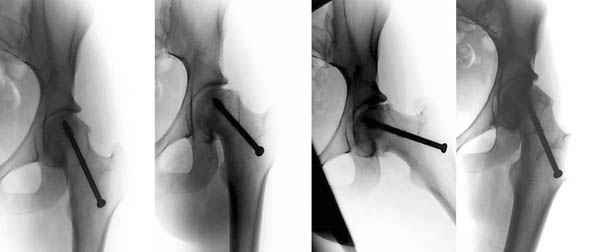

Ребёнок 14 лет. Весом под центнер. Имеющаяся рентгенологическая деформация деформация - на момент поступления. Госпитализирован ребёнок 14 лет. Мальчик, мягко говоря, крупный, гиперстенического типа сложения, ближе к десантнику. Весит 95 кг. Ожирение 2-й степени. Со слов больного - испытывает дискомфорт в области тазобедренного сустава в течение 3-х месяцев. На рентгенограммах - положение дел на момент поступления - конец мая. Укорочение конечности на 1,5 см. Ограничение внутренней ротации. Ходит, едва заметно прихрамывая на больную ногу. Эндокринологический статус находится в стадии обследования. Выполнена рентгенография в стандартных укладках, спиральная КТГ.Ясное дело, головка бедра <ушла> вниз и кзади. Пытающаяся <поймать> её шейка варизировалась и исполнила ретроверсию, создав изгиб во фронтальной плоскости. На рентгеноскопии - подвижность головки не определяется. Мальчик имеет далеко идущие планы на обустройство собственной жизни и образование. Крайне негативно относится к длительной иммобилизации и консервативному лечению. Загодя не согласен со снижением качества жизни в процессе лечения. Мнения коллег относительно дальнейшего лечения разделились. Успешность репозиции головки под наркозом - сомнительная в связи с имеющейся деформацией шейки бедра. Одни склоняются к тактике невмешательства - разгрузка больной конечности, ФЗТ , массаж, и т.д. Предлагают ждать завершения процесса <сползания> головки в условиях полной разгрузки, <тянуть> сустав до эндопротезирования как можно дольше. Другая группа коллег предлагает немедленную стабилизацию головки, что, кажется, правильно. Принимая во внимание анатомическое соотношение головки и шейки бедра, способ остеосинтеза так же вызвал массу споров, не приведших к единому и окончательному мнению. Пока дискуссия остановилась на стабилизации спицами Бека под контролем ЭОП, возможно с применением электродов для проведения электростимуляции слабыми импульсными токами. Техника проведения спиц, однозначно, будет сопряжена с техническими трудностями, обусловленными имеющейся деформацией шейки. Как бы Вы поступили, коллеги, в данной ситуации?Заранее спасибо. И прошу прощения за качество спимков. Буду отправлять их по очереди.

Здравствуйте Данил. По представленным рентгенограммамам и кт срезам Вы имеете дело хронической, стабильной формой ЮЭГБК. Шеечно- эпифизарная деформация выраженная, эпифиз отклонён кзади более чем на 70 градусов, практически до упора в межвертельную ямку, что характеризует её как тяжёлую степень. В выборе метода лечения мы придерживаемся следующей схемы:

Здесь представлен один из случаев остеотомии на шейке после остаточного явления юношеского эпифизиолиза из Flip Trochanteric доступа.